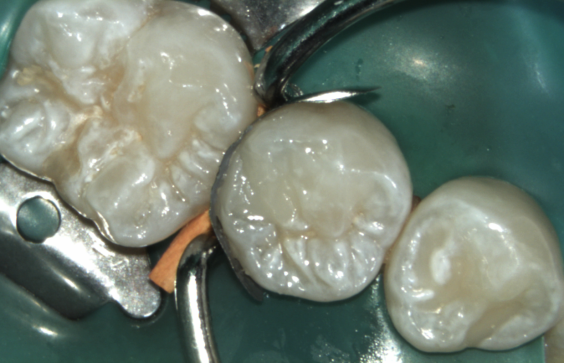

minimal-invasive<br />

Caries-Entfernung

minimal-invasive

hygienische Trocknung<br />

des Zahnes<br />

unter Cofferdam

hygienische Trocknung

des Zahnes